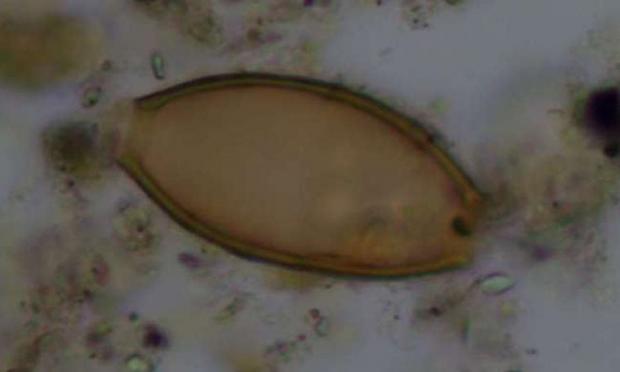

Η μελέτη αποκάλυψε σε τέσσερις από τους 25 σκελετούς (ποσοστό 16%) ότι μέσα στα αρχαία κόπρανα υπήρχαν υπήρχαν αυγά από δύο είδη εντερικών παρασιτικών σκωλήκων (έλμινθες): την ασκαρίδα (Ascaris lumbricoides) μήκους έως 30 εκατοστών και την τριχουρίδα (Trichuris trichiura) μήκους τριών έως πέντε εκατοστών. Το πρώτο παράσιτο βρέθηκε σε δείγματα από την εποχή του Χαλκού και μετά, ενώ το δεύτερο από τη νεολιθική εποχή και μετά.

Οι ερευνητές θεωρούν ότι η έρευνά τους έφερε στο φως μερικά από αυτά τα είδη των ιπποκρατικών παρασίτων. Πιστεύουν ότι η ασκαρίδα που βρέθηκε στην Κέα, είναι το ίδιο παράσιτο που περιγράφεται στα αρχαία ιατρικά κείμενα ως έλμινθα στρογγυλή.